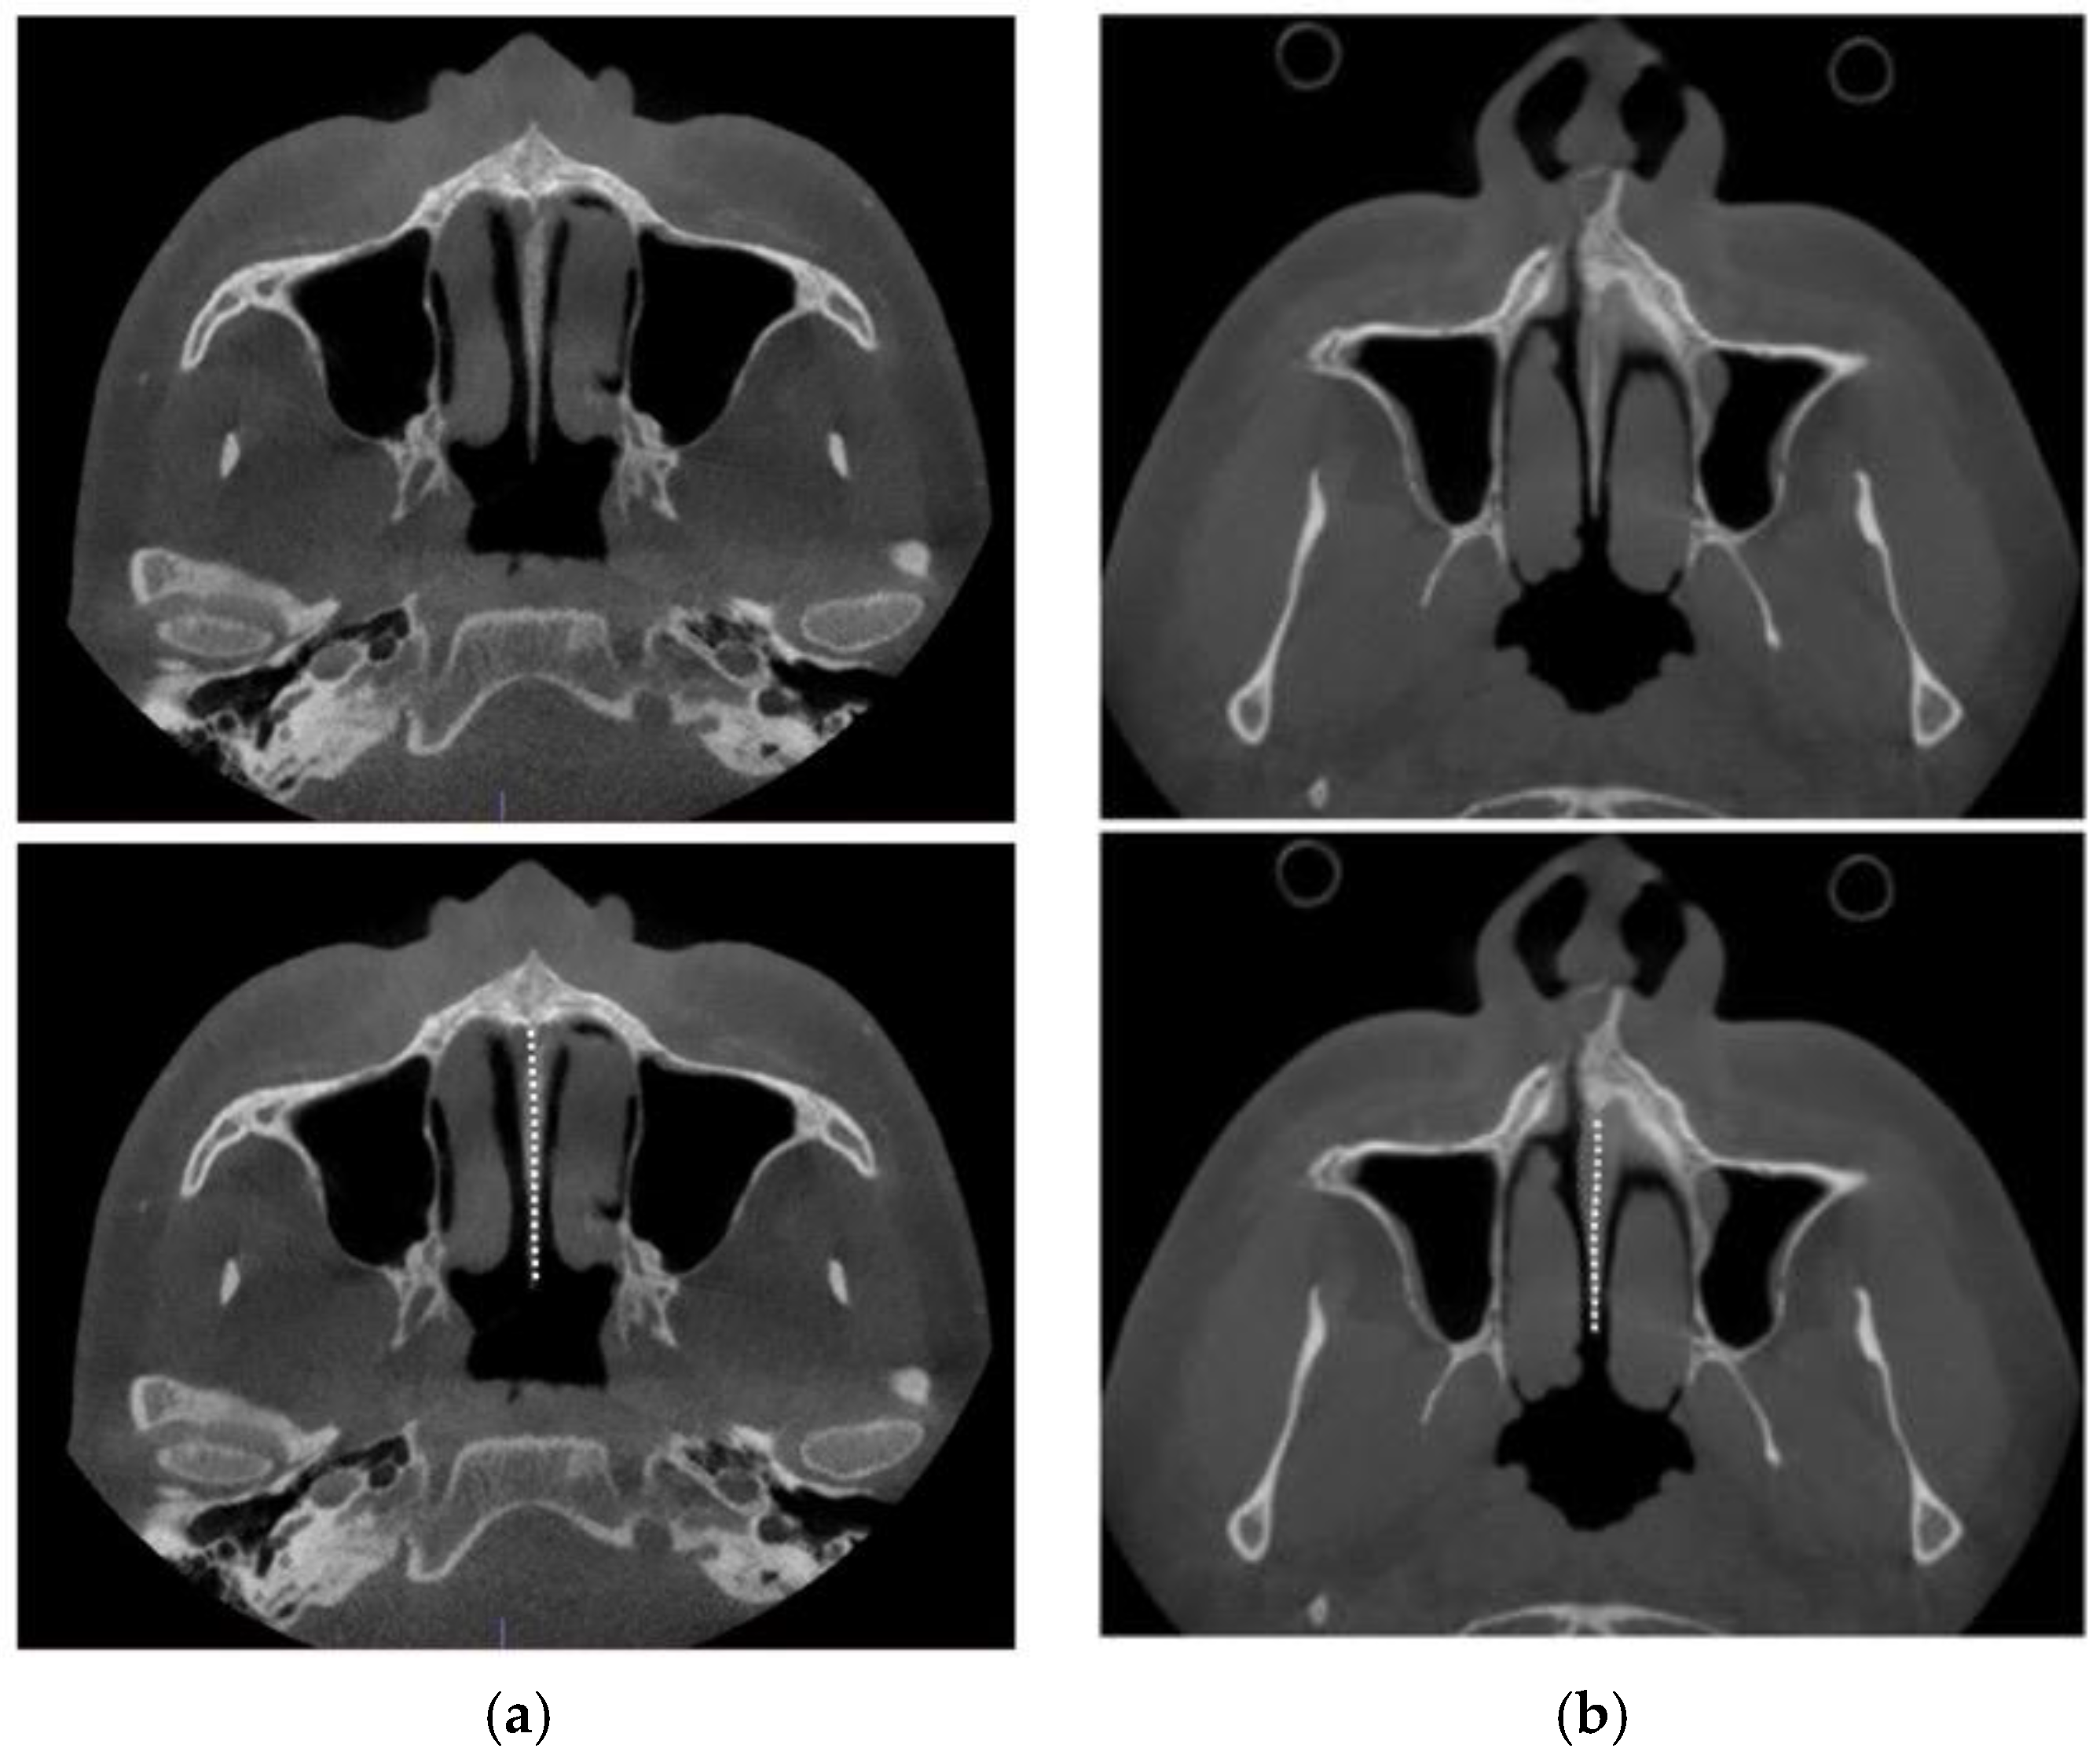

2.4. Case A: Blind Midpalatal Piezocorticotomy with MARPE Expansion

2.5. Case B: Guide-Assisted Midpalatal Piezocorticotomy

2.6. Case C: Bilateral Posterior Crossbite with Guide-Assisted Expansion

2.7. Case D: Midfacial Asymmetry Correction with Guided Expansion